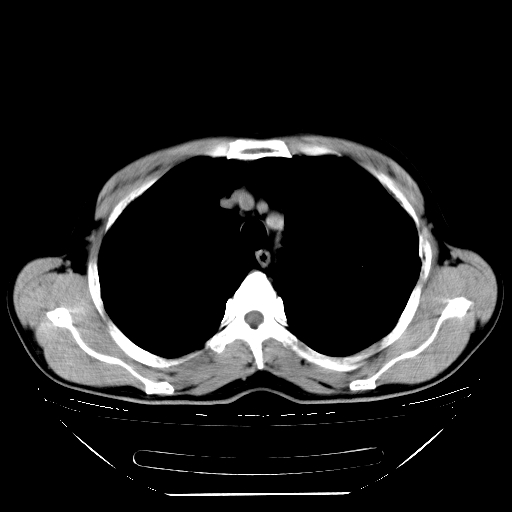

标题: CT21642:男,56岁,咳嗽、咳痰、右侧胸痛一周。 [打印本页]

男,56岁,咳嗽、咳痰、右侧胸痛一周,无发热。

纵膈窗关键层面不全。考虑右上肺继发性tb可能性大。建议查血沉、ppd,痰菌培养。

1)考虑右肺上叶继发性肺结核。2)两肺近胸膜下多发性肺大泡。

补传图像:纵隔窗已补传完。